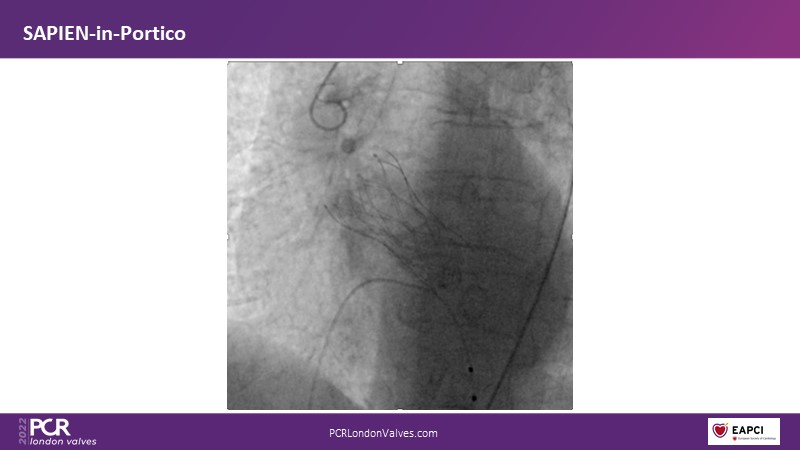

TAVI-in-TAVI - A road map for successful lifetime management

Join a team of experts that guide you through the basics of TAVI-in-TAVI, the procedural planning and techniques of implantation, followed by case examples with different index prostheses.